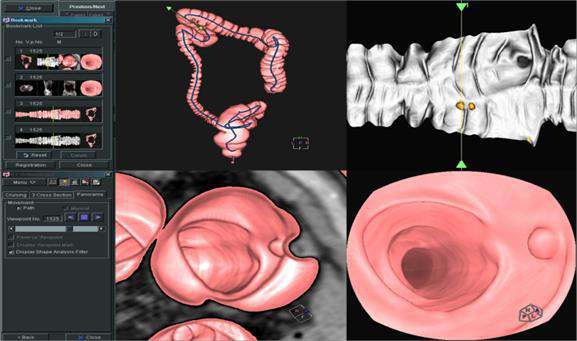

Apsaras憑借其傑出的掃描能力及豐富的自主研發臨床軟件已成爲業界新貴。

Apsaras 是具有全面表現力的 CT 系統,新産品其傑出的掃描能力及自主研發的臨床軟件的應用使産品集疾病的診斷、治療、預防爲一體,考慮醫生、使用者、受檢者的多重需要,開拓了全新的醫學領域。适用于急診、門診、病房以及臨床科研的全方位應用。